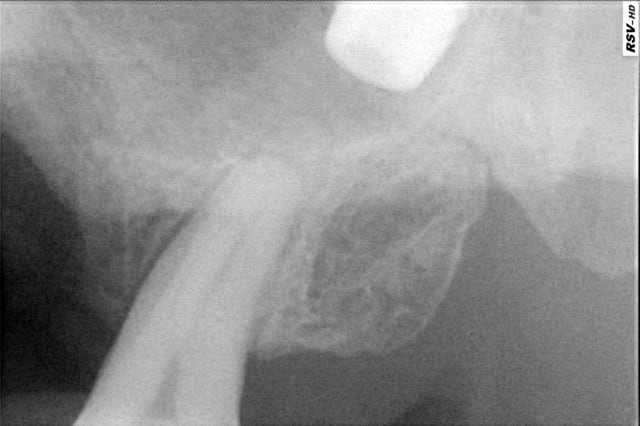

oui, c'est ça: fenêtre latérale et recherche. Mais entre la pano et le retour au fauteuil, je le trouvais plus! d’où la 2eme radio: il avait roulé au fond. du coup, j'ai mis la patiente assise, lui ai fait bouger la tête par quelques petits mouvement bref, ce qui l'a fait se replacer dans le bas fond. avec l'aspi, j'ai pu le ramener et l'attraper.

tu t'en es très bien tiré mais ton patient a très pue de chance lorsque l'on regarde la pano on s'aperçoit que même le canal a aspiré la pâte de traitement .